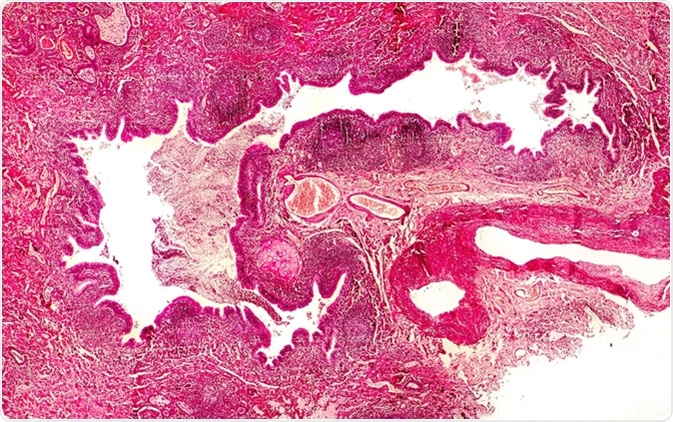

Bronchiectasis, cross-section through bronchus. Light photomicrograph showing dilatated and distorted bronchus containing pus - Image Credit: Kateryna Kon / Shutterstock